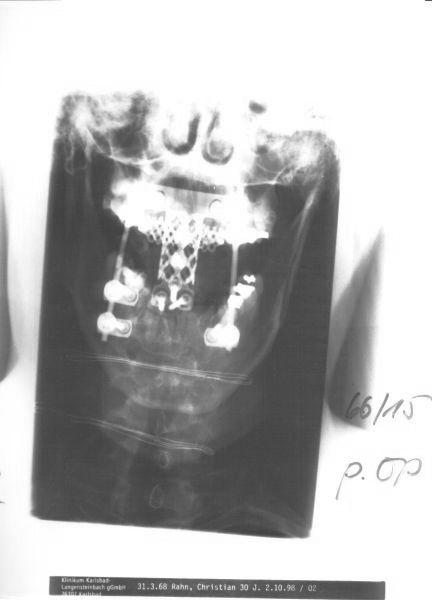

Mein Hals nach der OP (Entfernung des 2. Halswirbels)